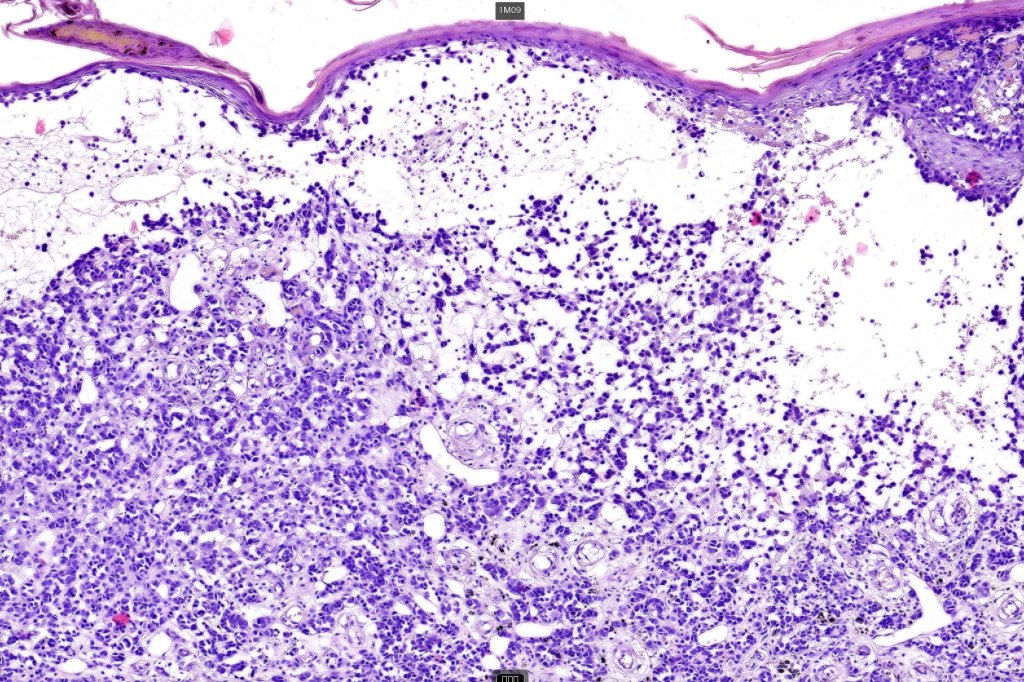

An exceedingly rare variant of melanoma. The term includes cases of melanoma that show features of an associated inherited bullous dermatosis such as epidermolysis bullosa or acquired immunobullous intraepidermal or sub epidermal bullous dermatosis such as pemphigus or bullous pemphigoid and cases where the blister develops directly overlying the melanoma in the absence of any underlying/associated blistering condition. It is generally recommended that measurement of the melanoma should be from taken below the blister/vesicle so as to avoid over-estimating tumor thickness.

Case courtesy of Dr. Antonina Kalmykova